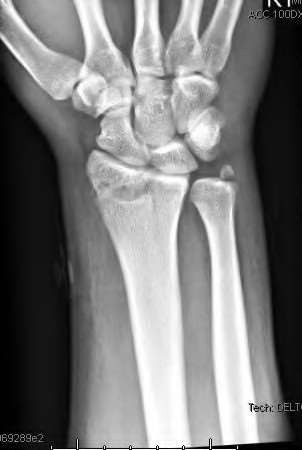

A 20-year-old park ranger trips and falls onto his right wrist with the wrist in extension and pronation. The local urgent care orders both radiographs and a CT, which you review and determine to be normal. The patient complains of ulnar-sided wrist pain. On exam, his tenderness is localized to the fovea. Ulnar deviation also causes him pain. There is no snapping sensation with wrist supination, flexion, and ulnar deviation. He otherwise has 5/5 strength to his first dorsal interosseous muscle with 4mm static two-point discrimination on the ulnar side of the 4th digit. Which of the following injuries is most likely responsible for his symptoms and exam?